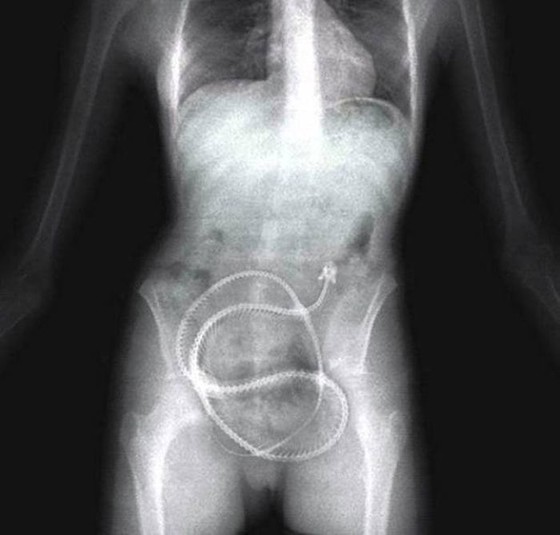

Предметы, которые не очень хочется видеть внутри себя

Под рентгеновскими лучами порой видны не только внутренние органы и кости, но и инородные тела, попавшие в организм

Истории попадания этих предметов в организм могут быть самыми невероятными и запутанными, но больше всего медиков интересует процесс их извлечения, впрочем, в этом заинтересованы и сами пациенты, допустившие нечто подобное со своим телом.